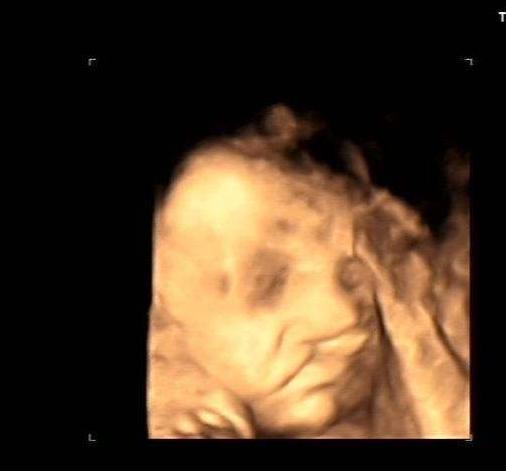

超声诊断胎儿唇腭裂

双胎宝妈21周做四维彩超,筛查出一名胎儿为"唇腭裂"

遗憾!安真四维彩超筛查出一例胎宝宝"兔唇"